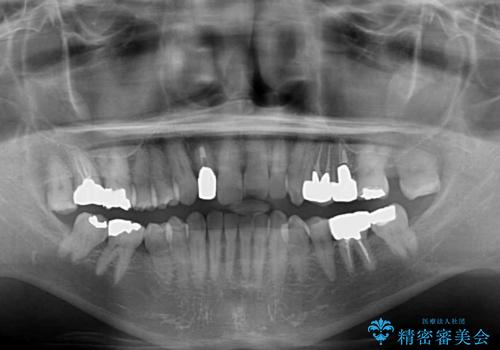

- 前歯のクロスバイトを気にして来院された患者様です。

骨格的に下顎が前方位ではありますが、歯並びが改善されれば正常咬合となることが分かったため、インビザラインを用いて咬み合わせを改善していくこととしました。